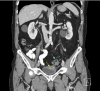

Figure 1. Coronal computed tomography of the abdomen and pelvis with intravenous and oral contrast (Gastrografin).

The image shows gas locules within the bladder (yellow arrow) and adjacent sigmoid diverticulitis (blue arrow) consistent with colovesical fistula.